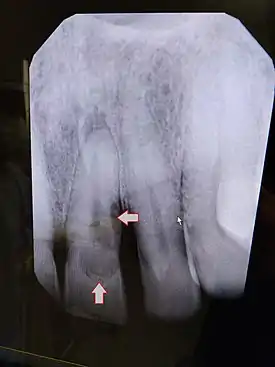

Post traumatic External tooth resorption 9 | |

Diagnostic method | Dental examination, X-rays |

External resorption is the loss of tooth structure from the external surface of the tooth and is further subcategorized based on its etiology.[16]

External inflammatory root resorption may be caused by trauma to the root surface, due to damage to the periodontal ligament (PDL) and/or extended drying following tooth avulsion. Following trauma, dentinal tubules are exposed leading to communication with an infective or necrotic pulp. This leads to an inflammatory process that causes external root resorption.[16]